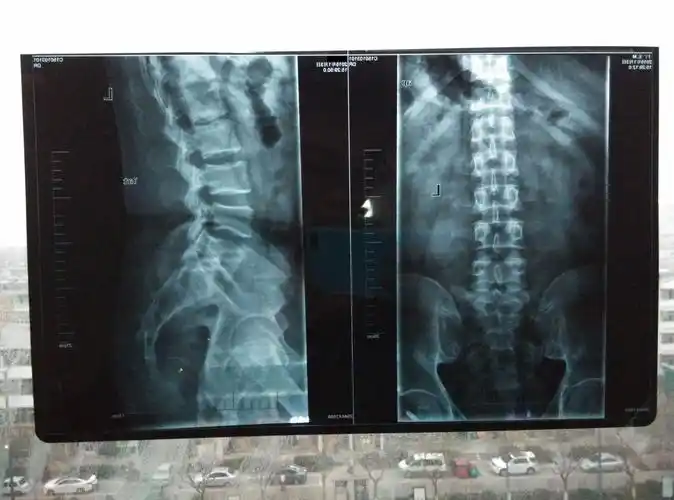

腰4/5椎间盘脱出高度向上游离病例分享——洛南县中医院骨科(副本)

典型案例二:男,48岁,腰椎间盘突出.